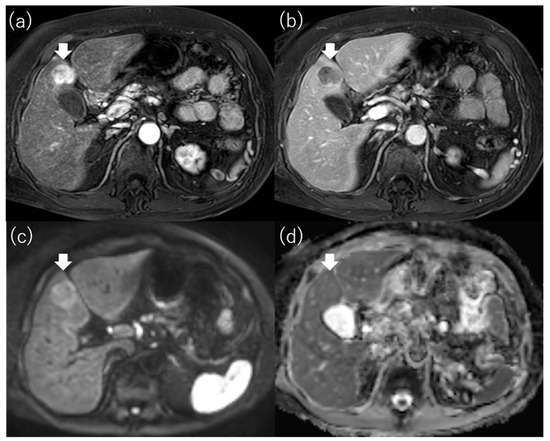

4.1. Enhancement Pattern in the Hepatobiliary Phase

4.2. Enhancement Pattern in the Arterial Phase

- Bae, J.S.; Kim, J.H.; Lee, D.H.; Kim, J.H.; Han, J.K. Hepatobiliary phase of gadoxetic acid-enhanced MRI in patients with HCC: Prognostic features before resection, ablation, or TACE. Eur. Radiol. 2021, 31, 3627–3637. [Google Scholar] [CrossRef]

| Lee et al. [53] | 345 | Solitary and ≤3 cm | LR (123) RFA (222) | Outcome (recurrence) | In RFA group, non-hypervascular hypointense nodule was one of the independent factors for recurrence (HR, 1.78; 95% CI, 1.20–2.63; p = 0.004). |

| Iwamoto et al. [54] | 91 | Early stage | RFA | Outcome (recurrence) | Non-hypervascular hypointense nodule was one of the independent factors for intrahepatic distant recurrence (HR, 4.37; 95% CI, 2.13–8.86; p < 0.01). |

| Toyoda et al. [55] | 77 | Early stage | LR | Outcome (recurrence) | Non-hypervascular hypointense nodule was an independent factor for multicentric recurrence (HR, 2.84; 95% CI, 1.69–4.84; p = 0.0002). |

| Toyoda et al. [56] | 138 | BCLC stage 0 or A | LR (76) RFA (62) | Outcome (recurrence, OS) | Non-hypervascular hypointense nodule was an independent factor for recurrence (HR, 1.68; 95% CI, 1.26–2.25; p = 0.0005) and which was one of the independent factors for OS (HR, 1.63; 95% CI, 0.99–2.81; p = 0.05). |

| Bae et al. [57] | 183 | BCLC stage 0 or A | LR (61) RFA (61) TACE (61) | Outcome (recurrence, OS) | In RFA group, existing satellite nodules was one of the independent factors for disease-free survival (HR, 5.04; 95% CI, 1.06–23.90; p = 0.04); moreover, peritumoral hypointensity (HR, 13.06; 95% CI, 1.63–104.84; p = 0.02) and existing satellite nodules (HR, 9.40; 95% CI, 1.48–59.67; p = 0.02) on HBP were related to OS. |